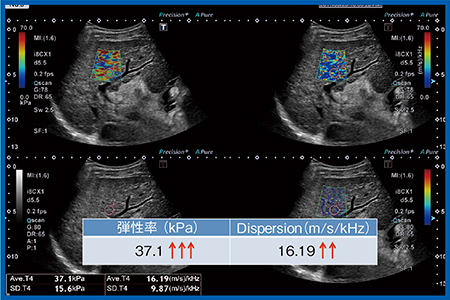

症例5(図12)はC型肝硬変症例で,弾性率は37.1kPaと非常に硬いが,Dispersion slopeは16.19m/s/kHzと,それほど上昇していなかった。

改めてNASH LC症例(図11)とC型肝硬変症例(図12)を比較すると,C型肝硬変症例では弾性率が非常に高値であるが,それに比してDispersion slopeはあまり高くない。一方,NASH LC症例は,弾性率はそれほど高くないが,Dispersion slopeは非常に高い。今後は,なぜこのようなことになるのかを,病理組織所見と併せて解明していくことが必要と考えられる。

図12 症例5:C型肝硬変症例の弾性率とDispersion slope

Plt 11.3万,AST 85,ALT 62,T-Bil 0.94